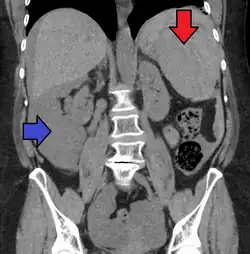

Traumatic rupture of the spleen on contrast enhanced axial CT (portal venous phase)

Splenic hematoma resulting in free abdominal blood